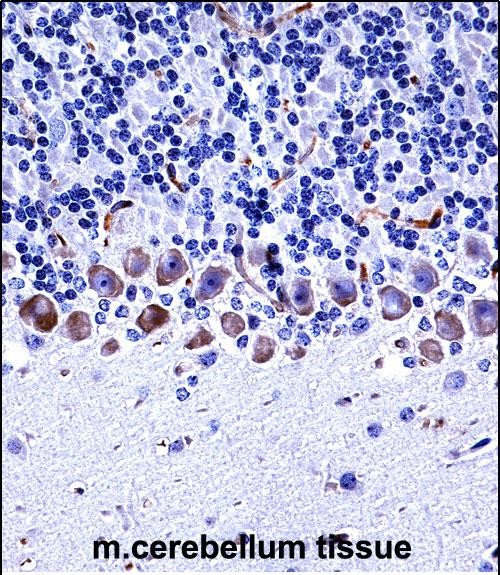

| IHC | 1/100-1/500 | Human,Mouse,Rat |

| Immunogen | This Mouse Epha4 antibody is generated from rabbits immunized with a KLH conjugated synthetic peptide between 464-492 amino acids from the Central region of mouse Epha4. |